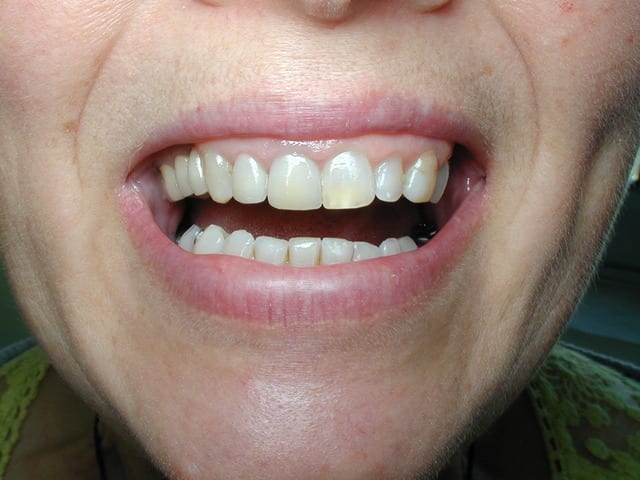

je pense que la structure de cette dent n estpas homogene , qu elle est sous cuite ; et que la dent na pas ete degraissee avant glacage le materiau emax est le plus facile a glacer ci joint 2emax 11 12 et deux emax 11 21 merci

Ber la céramique emax est très sensible à la cuisson et très souvent les protho cuisent mal leurs céramique car ils font le programme marqué qu il y est une ou 10 dents dans le four et aussi la position de la dent dans le four est très important donc si la première cuisson est ratée la dent est ratée et souvent sous cuite. Donc porosités !... Et il faut aussi faire attention au glaze ivoclar pour l emax il accentue. Les bulles de surface. Et voilà le résultat.

c'est clair manque de polissage avant glaçage, et la glaz n'a pas été suffisamment appliquée, sur l'Emax faut impérativement effectué un polissage mécanique de surface avant glaçage sinon vous voyez le résultat

L'emax Céram de stratification n'est pas une céramique simple à utiliser.

Les états de surface naturels et exempts de porosités que l'on arrive à obtenir avec les autres céramiques sont réellement moins facilement obtenables avec l'emax.

Tout dépend des programmes utilisés, des liquides de montage, des fraises diamantées, de la glaize, du rapport épaisseur d'armature/épaisseur de cosmétique.

Au final si je reprends les photos de mes premiers cas il y a 6 ans et maintenant l'expérience fait que je n'ai plus de porosités de surface.